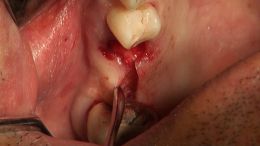

اصول مبانی GBR

+ اساتید گروه علمی بن تاژ پارس (زیرنظر پروفسور غلامی)

- جراحي توسط دکتر عميد از اساتید گروه علمی بن تاژ